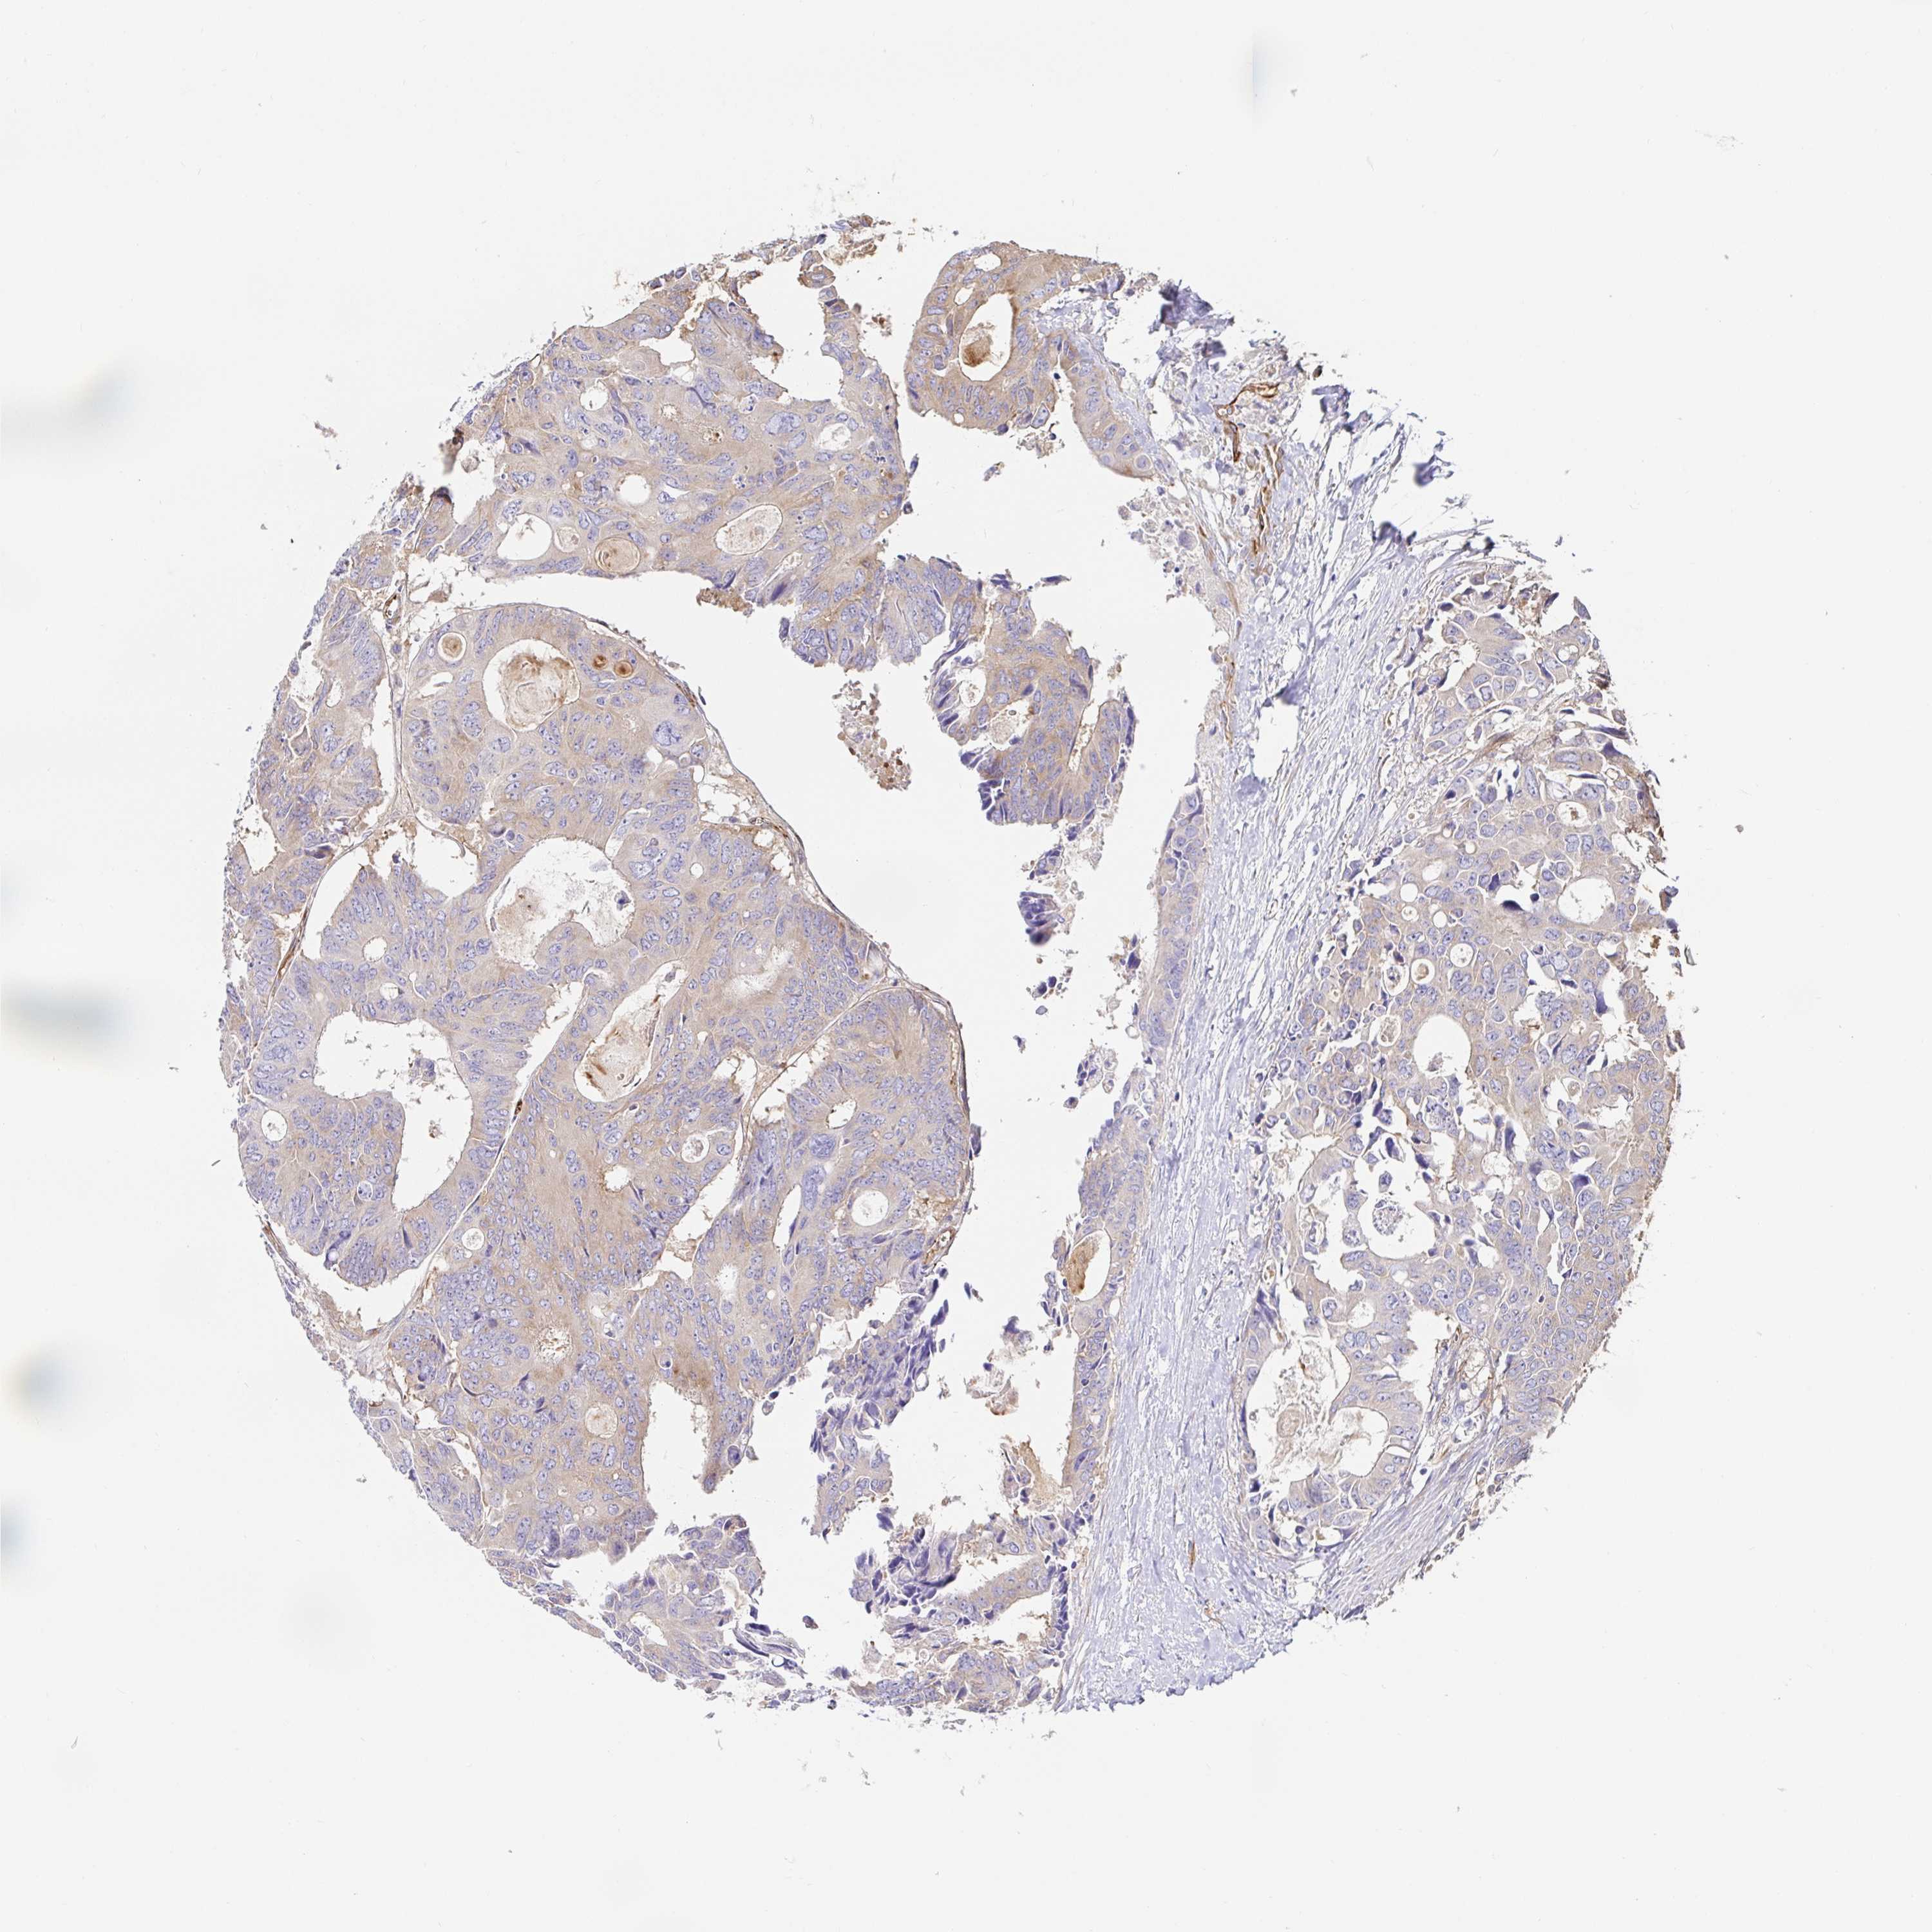

CANCER COLORECTAL CANCER Show tissue menu

Colorectal cancer

Human cancer

Colon adenocarcinoma